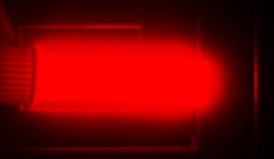

| Bright light emission from silicon quantum dots in a cuvette. The image is from a camera that captures the near-infrared light that the quantum dots emit. The light emission shown is a psuedo color, as near-infrared light does not fall in the visible spectrum. Credit: Folarin Erogbogbo |